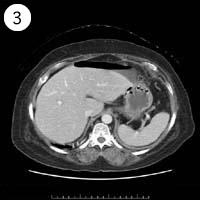

57歳 女性

単純CT

造影CT